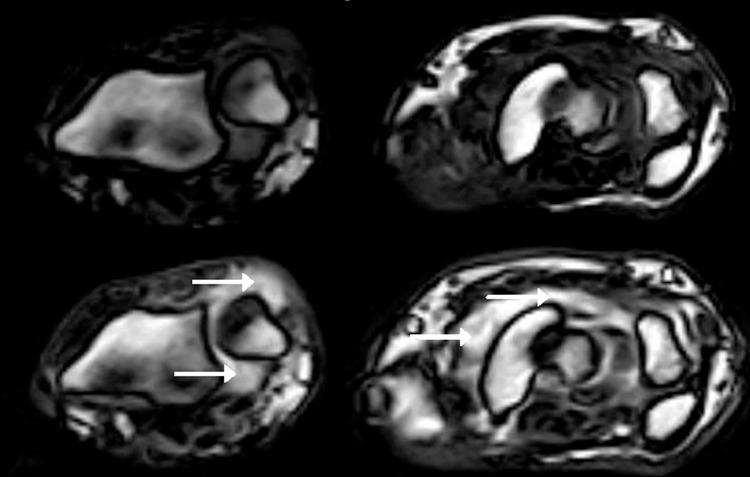

Clinical remission has become an achievable target for the majority of patients with rheumatoid arthritis, but subclinical inflammation as assessed by ultrasound and magnetic resonance imaging (MRI) has been demonstrated to be frequent in patients in clinical remission. Subclinical synovitis has been shown to be linked to both subsequent structural damage progression and a risk of flare, demonstrating that subclinical synovitis represents incomplete suppression of inflammation and questions whether it is appropriate only to use clinical composite scores as treatment target in clinical practice. Maintaining a state of remission has proven important as sustained clinical remission impacts long-term outcome regarding joint damage progression, physical function and quality of life. Treating subclinical inflammation has been attempted and has led to more frequent strict clinical remission and better physical function, but also to more adverse events. Thus, an overall benefit of incorporating imaging goals in treat-to-target strategies has not been documented. However, in patients in clinical remission on biological disease-modifying anti-rheumatic drugs, both ultrasound and MRI may aid in the clinical decision regarding whether drug tapering or even discontinuation should be attempted.